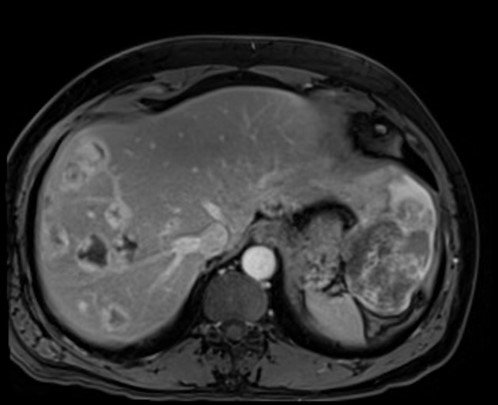

The largest lesion is located in the left lobe of the liver, segment 3, and demonstrates isointense signal compared to liver on T1 weighted images and no signal drop out on out-of-phase imaging to suggest presence of fat.

T2 :Hypo to slightly hyperintense

Central scar

T1 C+ (Gd)

heterogeneous enhancement with progressive filling